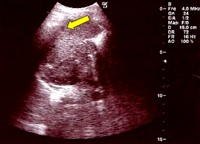

Si decide di eseguire l�ecografia addominale che a livello della milza evidenzia plurime e diffuse piccole zone ipoecogene (Figura 2). All'ilo epatico e in sede periportale evidenza di alcuni linfonodi ovalari, con diametro compreso entro 2 cm. Nella norma il parenchima epatico.

Figura 2. Ecografia Splenica. Milza con ecostruttura disomogenea per la presenza di plurime e diffuse areole nodulari ipoecogene, del diametro compreso tra 8 e 15 mm di non univoca interpretazione (foci flogistici?).